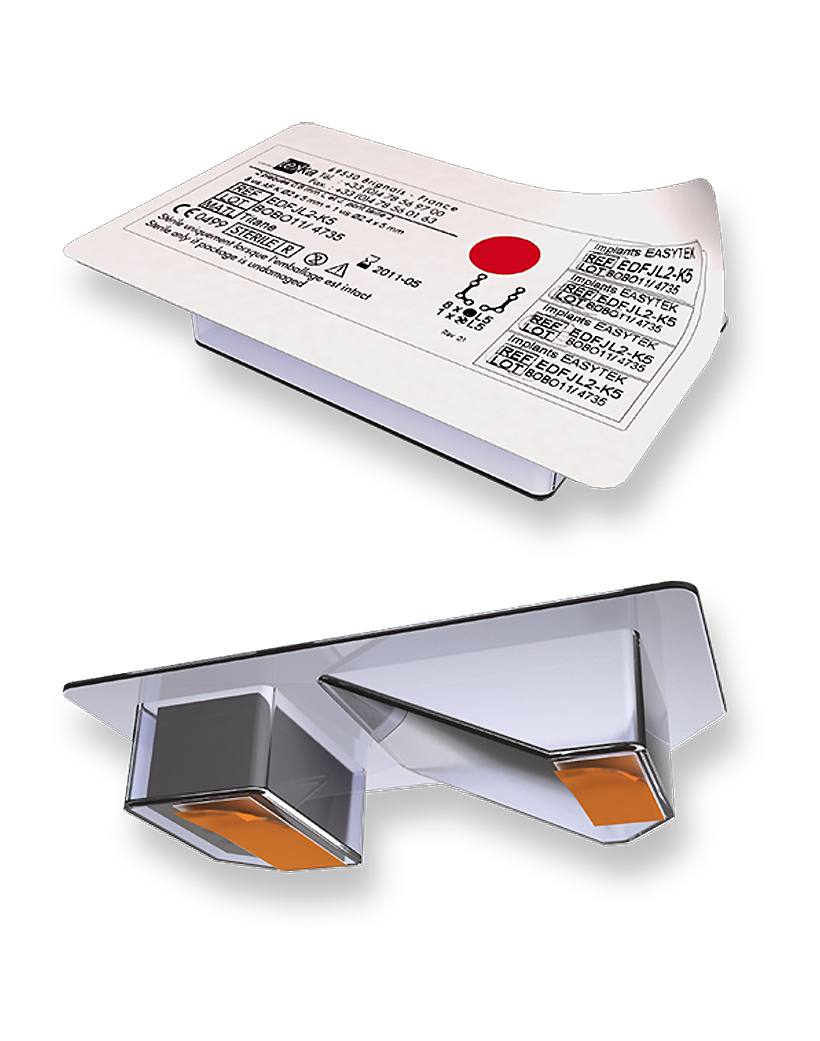

ORTRAUTEK est une gamme complète, dédiée à la chirurgie orthognathique, génioplastie, traumatologie et petite reconstruction.

Il s’agit d’un très large panel de vis et de plaques de différentes formes se déclinant dans des épaisseurs et des grades de titane distincts, le tout aisément identifiable grâce à un code couleur.